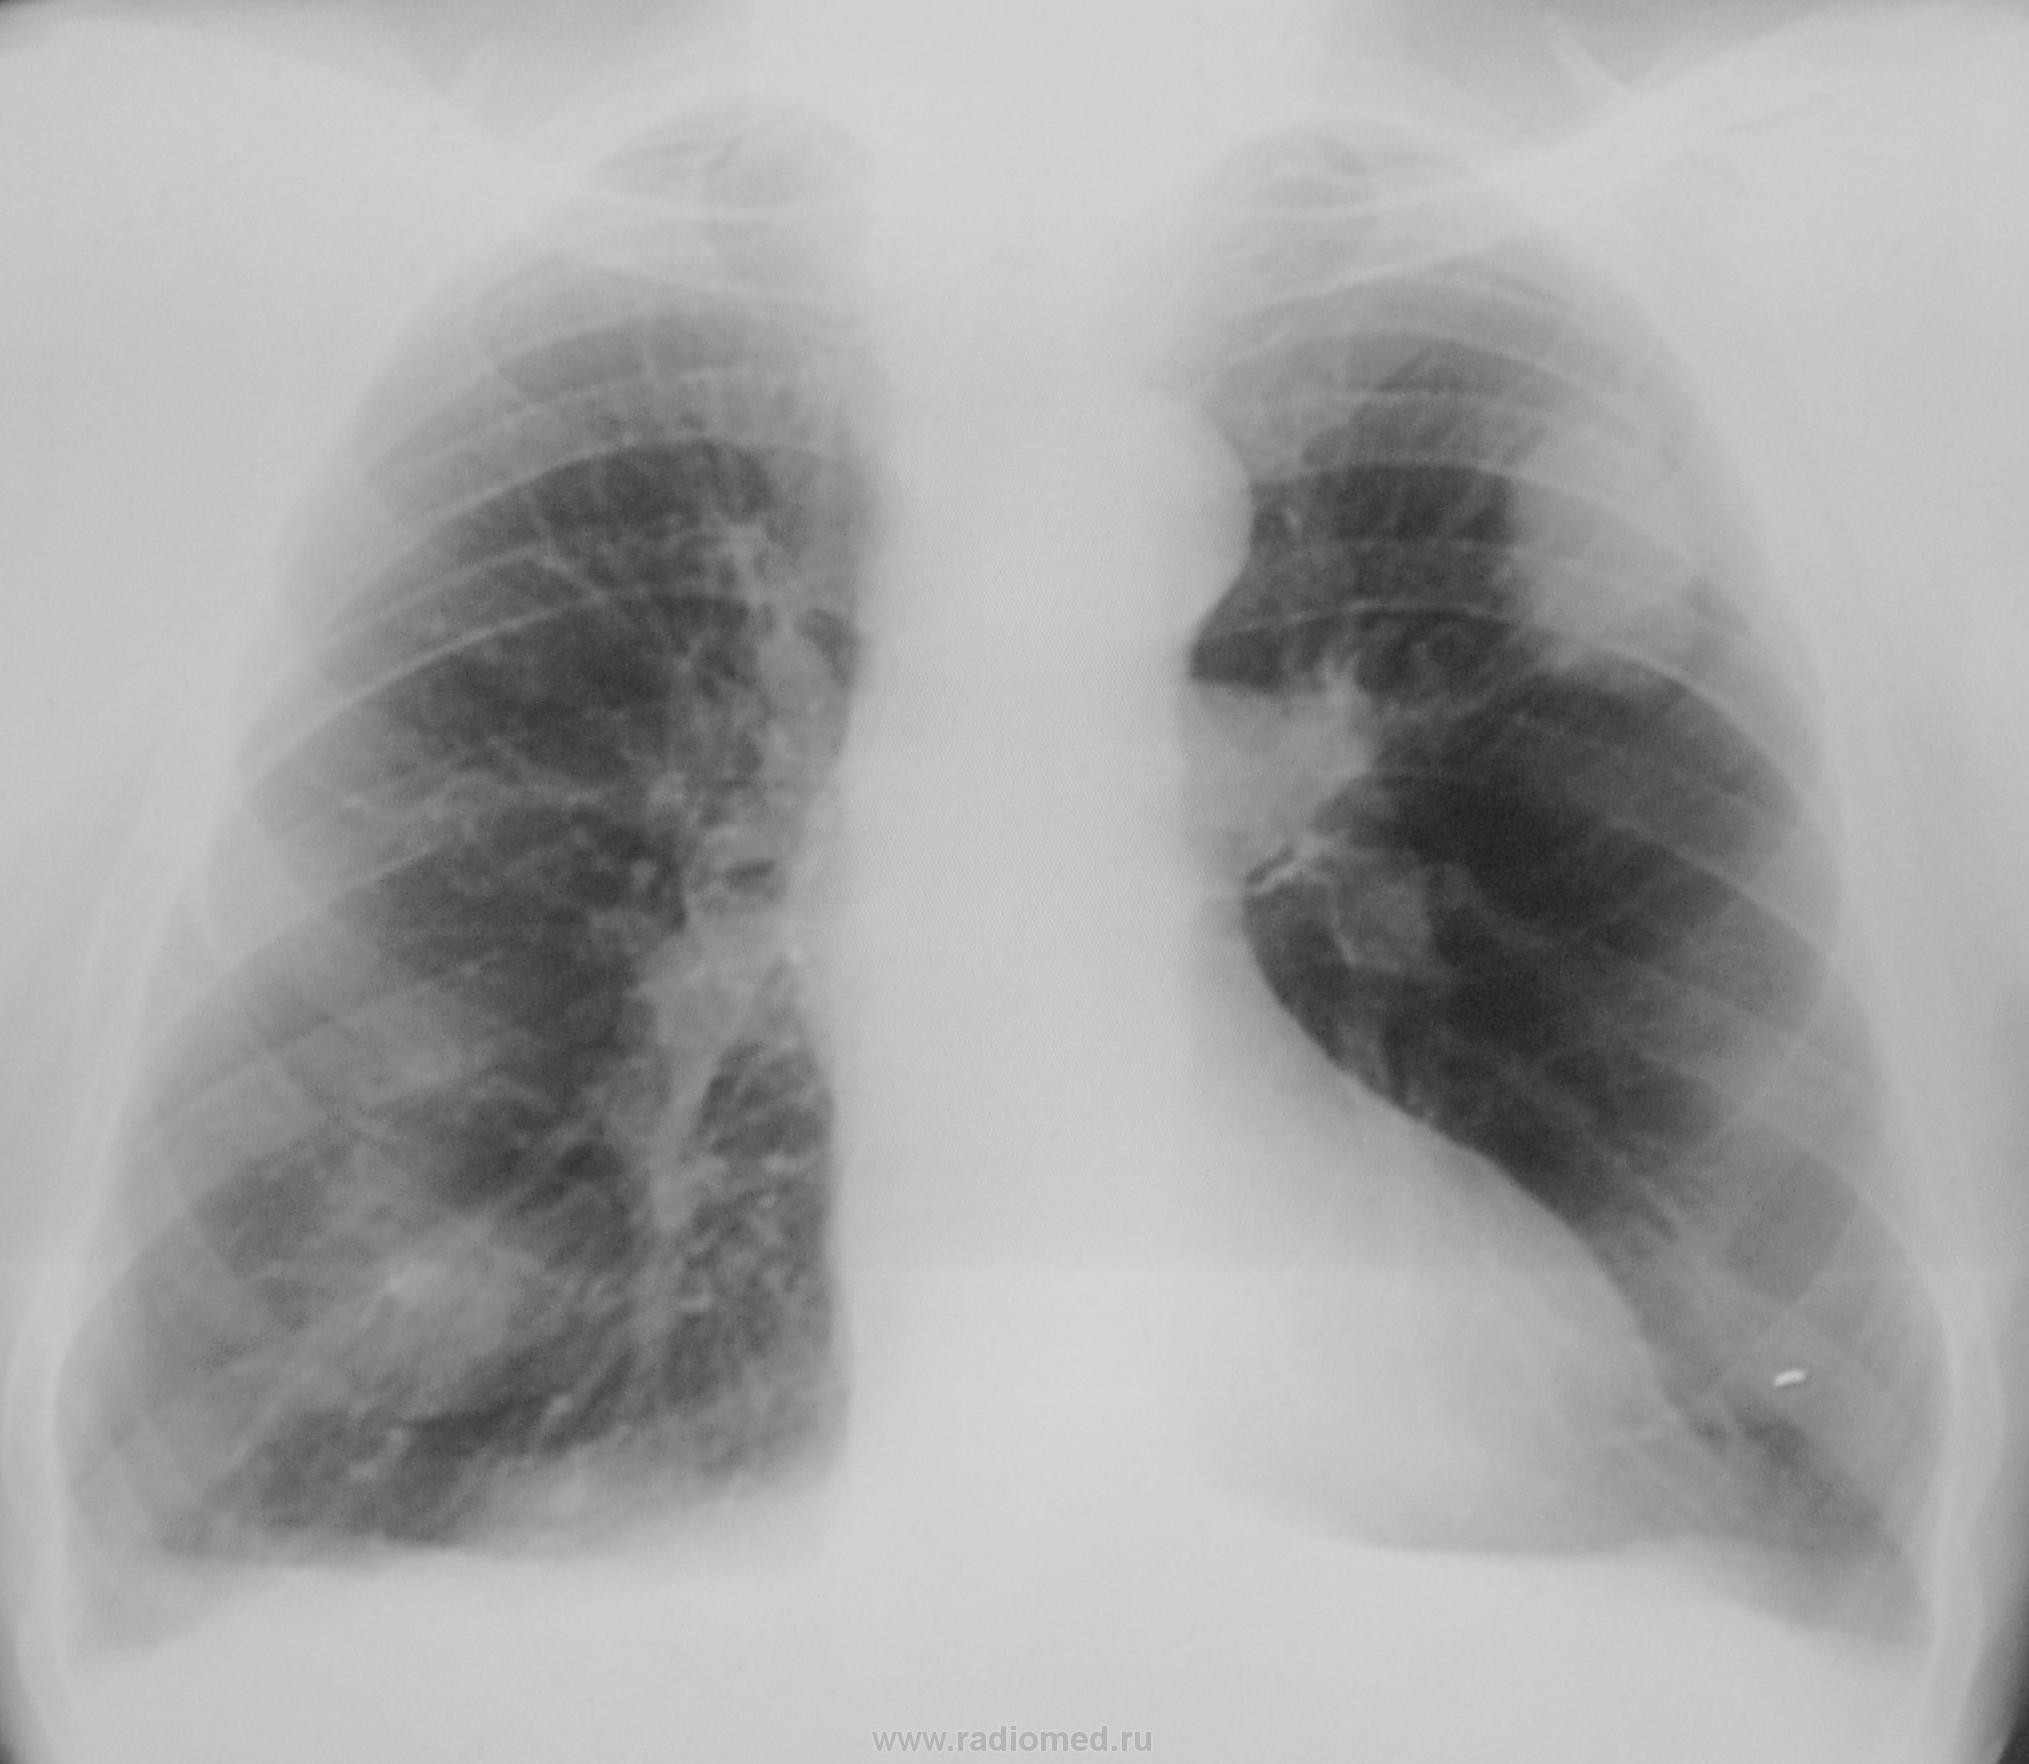

Такенная "балябуха" из ничего до такой "гули" выросла за год?

ретенционная киста. Не лежит душа к раку. Но,следует не забывать о нем. Желательно услышать голоса наших специалистов по онкологии. Nikolas

Может Вы и правы. Но на мой взгляд, сурьёзности и солидности совсем в этой тени нет. Прямо глянуть в "фейс" содрогнуться можно о размеров "балябухи" и на "томках", более, или менее нормально отобразилась только на двух срезах (шаг томографирования - 2 см), а я ведь резать с семерки начал до пятнадцатого, и только на двух срезах тело тени получил, а на всех остальных срезах - или нет, или безконтурная муть...

морфологическая верификация диагноза. Какие доводы в пользу заполненной ретенционной бронхогенной кисты легкого были у меня? Излагаю. Я предположил кисту при поступлении на сайт рисунка №1. Заметил, что она напоминает "гроздь винограда", что описано было давно в русской литературе. После этого, я вернулся к рисунку №2 и обратил внимание на вытянутую двояковыпуклую форму тени по ходу бронха. Затем ещё раз просмотрел рисунок №3, где отчетливо видно уже две тени, напоминающие растянутые и заполненные мелкие бронхи. После этого внимание привлекли четкие контуры "грозди", неизмененный окружающий фон, однородная структура тени, а также локализация тени в субаксиллярном сегменте. Не увидел я и реакции регионарных лимфатических узлов к корне левого легкого. К рентгеновской картине добавил очень быстрый рост тени и то, что больной выявлен при проверочной флюорографии (значит болезнь протекает бессимптомно). Все эти признаки, вместе взятые, дали мне возможность предположить ретенционную бронхогенную кисту легкого. Не исключаю, что мое заключение не совсем точное. Вы, уважаемый Валентин Львович задали вопрос. Я на него Вам ответил. С уважением Nik.

По всей видимости, уважаемые Виктор Григорьевич, мы не будем делать КТ, не все так просто и однозначно с КТ. Мы весьма оперативненько проконсультируем этого пациента, который, кстати, ни на, что не жалуется, вид его весьма здоров, в диагностическом отделении ОПТД, где имеются весьма большие диагностические возможности, а чтобы не отказали, возьмем, да и выставим ему "инфильтративный"..., ведь скиалогически в д/д ряду и он не может быть, вот так, сразу отвергнут, вот мы и воспользуемся этот благодатной возможностью...